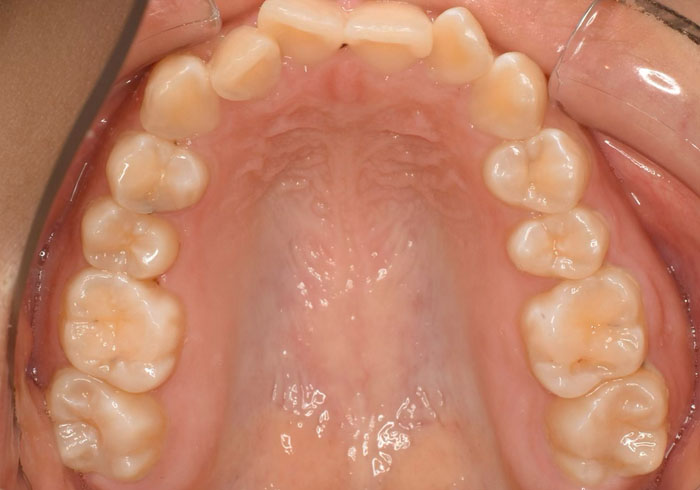

口腔内写真

治療前

マウスピース矯正 マウスピース矯正 マウスピース矯正